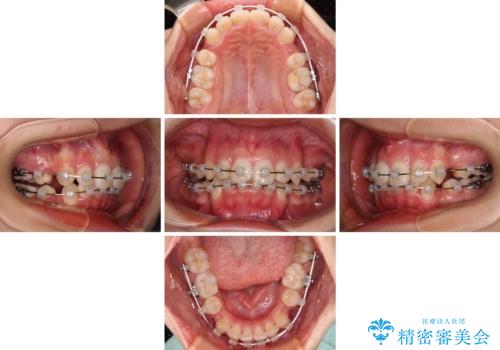

- 矯正装置

- クリアブラケット

補助装置を用いて奥歯の咬み合わせを改善しながら歯列を後方に移動させ、上下左右第一小臼歯を4本抜歯することで八重歯や口元の突出感を改善することとしました。

奥歯の咬み合わせの不正が顕著であったため、表側のワイヤー装置を選択して矯正治療を行うこととしました。